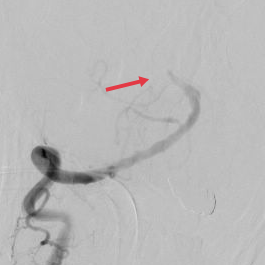

脑血管造影可见基底动脉闭塞

右侧椎动脉取栓后可见基底动脉“线样征”。